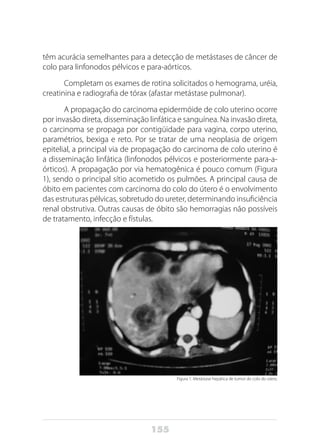

o tumor se desenvolve. O tumor que se localiza na cabeça do pâncreas

apresenta como sintoma comum a icterícia acompanhada de prurido e

que é decorrente da compressão extrínseca do ducto biliar. A compres-

são dessa via faz com que a bile retorne para o fígado e, em seguida,

para a circulação sangüínea, causando icterícia. Entretanto, esse sinal clí-